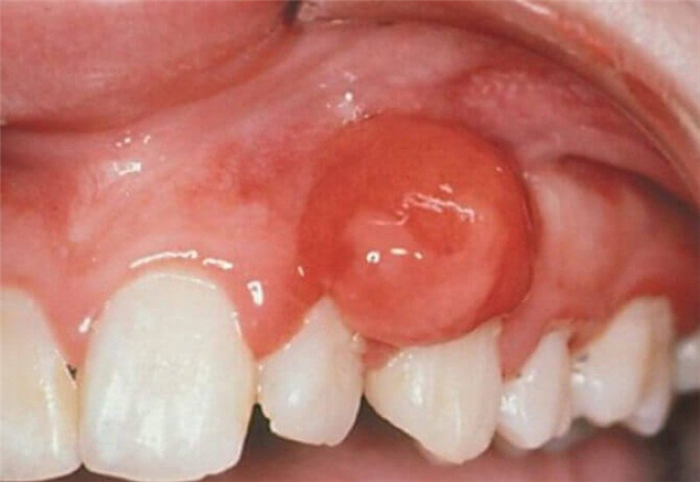

Клинически ФПР-новообразования представляют собой округлый опухолевый узел, размещенный на ножке или широком ложе. Он имеет бледно-розовую окраску, гладкую поверхность. При пальпации – безболезненный.

ФПР-образования отличаются медленным ростом (размер их редко превышает 2 см), покрыты эпителием и имеют четкие границы. Больные могут жаловаться на дискомфортные ощущения, связанные с присутствием этих новообразований.

В случае травмирования ФПР-образований их поверхность приобретает белесоватую или ярко-красную окраску.

Опухоль на внутренней стороне губы

Фиброма от раздражения — одно из наиболее частых доброкачественных образований полости рта. Она образуется в результате реактивной гиперплазии в ответ на хроническое раздражение. Несмотря на свое название, это не истинная опухоль. Истинные фибромы полости рта наблюдают редко. Фиброма от раздражения — бледно-розовая папула с чёткими границами, которая медленно растёт, превращаясь в узелок. Она имеет правильную округлую форму, широкое основание, плотную консистенцию и при пальпации безболезненна. Иногда в результате повторной травмы фиброма от раздражения приобретает белесоватый цвет, поверхность её становится неровной и может изъязвиться. Локализуется фиброма от раздражения на слизистой оболочке щеки, губы, десны или языка. При гистологическом исследовании фиброма представляет густое переплетение коллагеновых волокон под истончённым эпителием. Лечение заключается в устранении раздражающего фактора и экономном иссечении. Фиброму от раздражения наблюдают в основном у взрослых. Иногда при неполном иссечении она рецидивирует. При туберозном склерозе образуются множественные ангиофибромы. Это заболевание наследуется по аутосомно-доминантному типу и проявляется также судорожными припадками, умственной отсталостью и наличием ангиофибром на лице.

Фиброма в ротовой полости имеет вид шаровидного образования, безболезненного на ощупь. Новообразование держится на невысокой ножке, поэтому выступает над поверхностью. У опухоли гладкая поверхность и полностью отсутствуют наросты, эрозии или какие-либо видимые изменения слизистой оболочки. Фиброма, как правило, достаточно медленно и относительно незаметно для носителя растёт и увеличивается в размерах. Если опухоль не была травмирована, она может некоторое время пребывать в «спокойствии», сохраняя свой обычный размер. Если же травмирующий её фактор не был устранён, со временем возможно образование на её месте злокачественной опухоли.